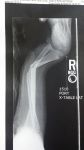

So, I was just minding my own business, not bothering anyone, when this boulder climbing wall comes along and.....you know..... starts making me climb it.  Yada Yada Yada, two plates and 11 screws later, I am laying back in the recliner being thankful it was not worse!

Yes that is the before shot. I have not seen it since the surgery, so I am looking forward to that! Just trying not to overdo the Oxycontin and checking back here for inspiration.

I can't look at your foot and ankle for long ... it makes me queasy ... it looks soooo damn painful ... unh ...

Max's 1st and 2nd injuries = all in 6 months time!

break #2.jpgbreak # 1.jpglittle boy.jpg